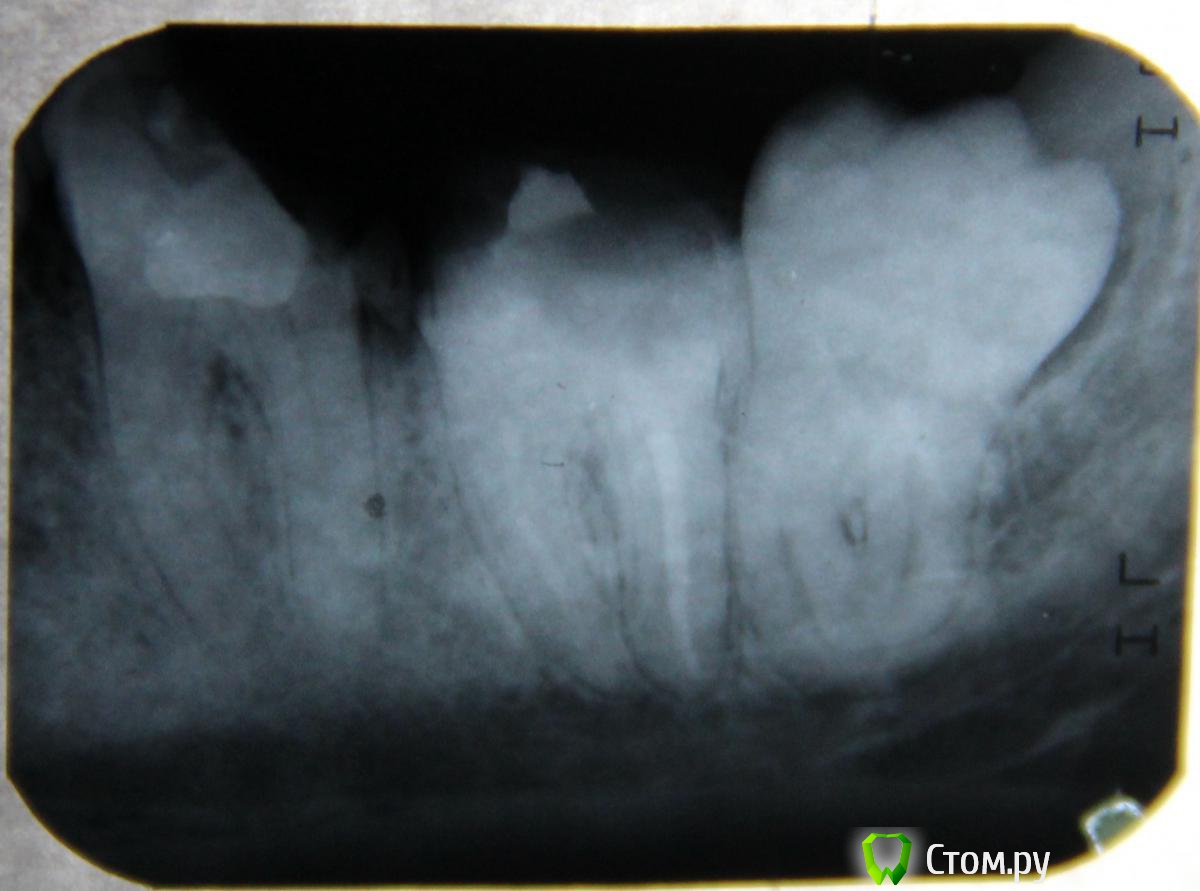

Екатерина Литвинова Опубликовано 20 февраля, 2014 Автор Поделиться Опубликовано 20 февраля, 2014 Ждем снимки. Без снимков ничего сказать не могу В идеальном варианте - панорамный снимок.Вот сделала. Ссылка на комментарий

Екатерина Литвинова Опубликовано 20 февраля, 2014 Автор Поделиться Опубликовано 20 февраля, 2014 Да, через радикал. Вторая ссылкаhttp://radikale.ru/data/upload/05615/c2184/e28261a877.jpg спортивное питание Ссылка на комментарий

red_butler Опубликовано 20 февраля, 2014 Поделиться Опубликовано 20 февраля, 2014 Удалил бы мудрый зуб. И с шестым седьмым разбирайтесь 2 Ссылка на комментарий

IvanK Опубликовано 21 февраля, 2014 Поделиться Опубликовано 21 февраля, 2014 Вы меня пугаете!!!А там что такое страшное?что страшное?разрушиенные зубы...8 ку на удаление, 7ка не далеко от нее ушла. боюсь попросить сделать панорамный снимок.@Екатерина Литвинова, Вам нужно срочно заняться зубами, а не рассуждать о "капюшонах".. 2 Ссылка на комментарий

Bier Опубликовано 1 марта, 2014 Поделиться Опубликовано 1 марта, 2014 на мой взгляд и 7 и 8 на удаление. 1 Ссылка на комментарий